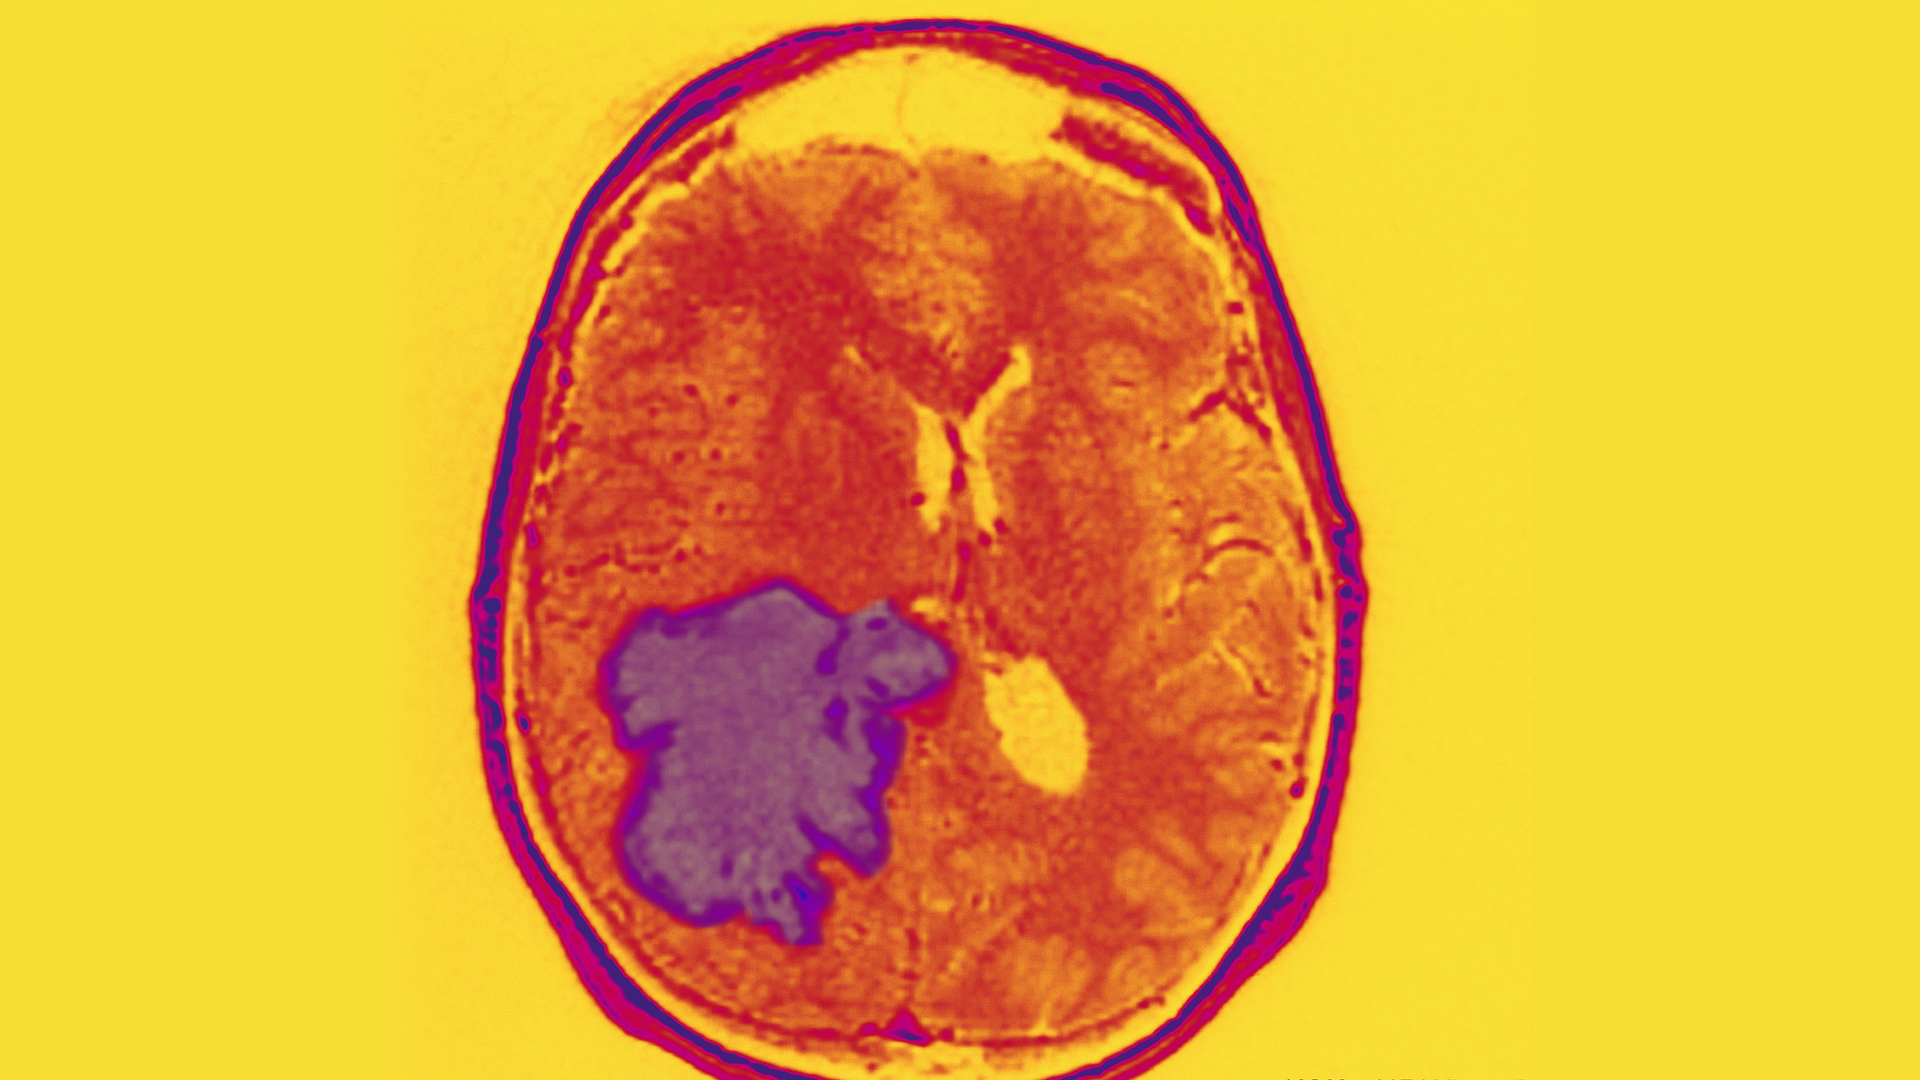

MRI of a patient with a glioblastoma tumor. Photo: BSIP/UIG via Getty Images

Why it matters: The targeted brain cancers — adults' glioblastoma and children's medulloblastoma — are aggressive cancers often fatal within 2 years (as seen when glioblastoma claimed the life of Sen. John McCain). This team hopes this new method, which successfully breaches the blood-brain barrier, may be an important step forward in finding an effective treatment.

Background: Glioblastoma and medulloblastoma tumors are often deep in the brain where it's difficult to surgically remove them. Immunotherapies are thought by many to offer great promise in treating the tumors, but they face many challenges, including safely breaching the blood-brain barrier.